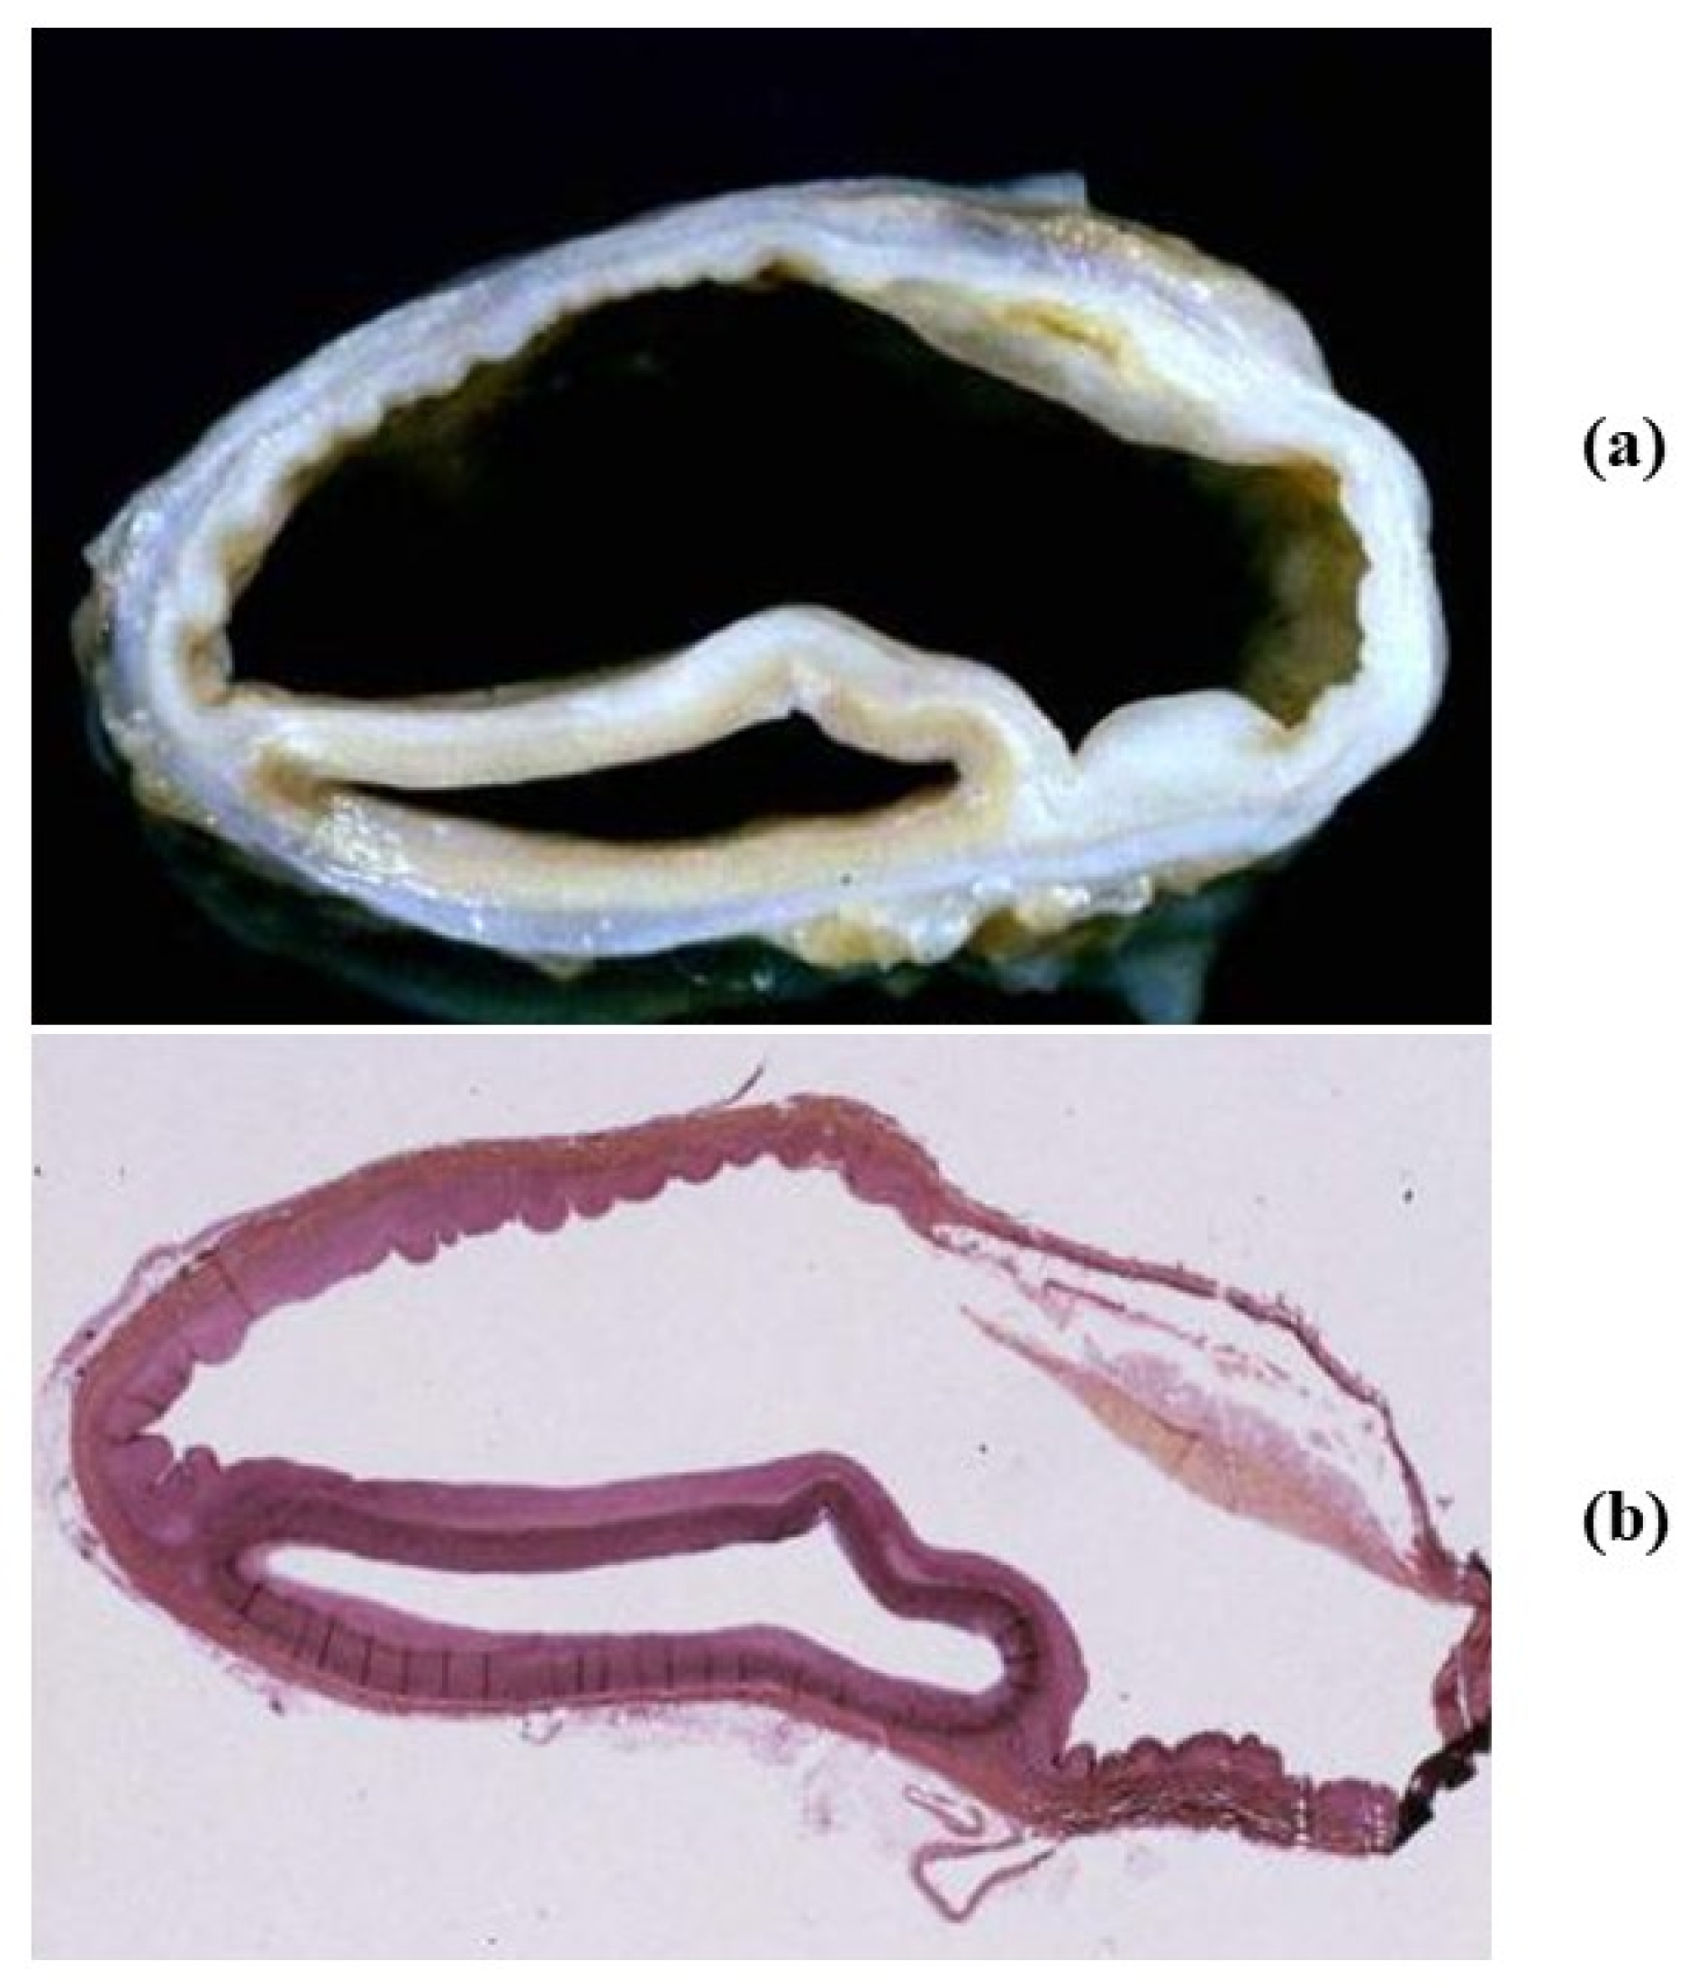

- Decellularization in unimplanted allografts appeared complete, both in the lamellar units of the tunica media and valvular interstitium with disappearance of endothelial lining (Figure 31);

- Cellular repopulation was observed in the outer part of implanted homograft wall by novel smooth muscle cells in the lamellar units (Figure 32a,b) and in the intima with a novel myointimal layer; this layer was noticed also in small animals such as rodents [68]. Novel endothelial cells appeared to line both the aortic wall intima and inflow/outflow at the cusp surface, as well as vasa vasorum, and valve spongiosa appeared repopulated by interstitial cells (Figure 32c,d);